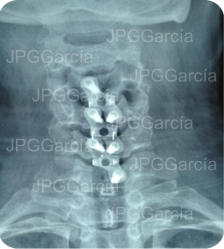

Tratamiento neuroquirúrgico con colocación de cajas intersomáticas

cervicales hasta 3 niveles por vía anterior vistas anteroposterior y lateral

Tratamiento neuroquirúrgico

con colocación de cajas

intersomáticas cervicales hasta

3 niveles por vía anterior vistas

anteroposterior y lateral